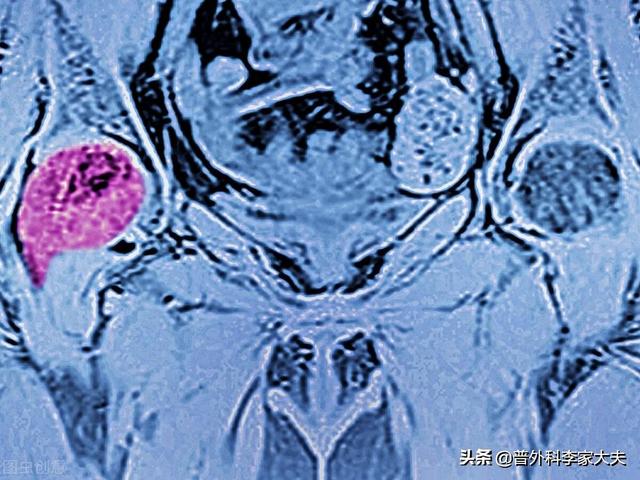

この患者だ。左股関節痛、大腿骨頭壊死を心配したが、肺がん骨転移と判明。